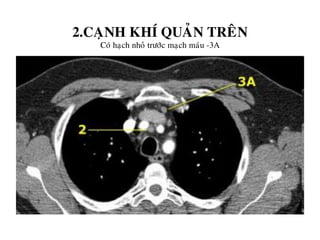

2.CAÏNH KHÍ QUAÛN TREÂN

Coù haïch nhoû tröôùc maïch maùu -3A

3. HAÏCH TRÖÔÙC MAÏCH MAÙU VAØ TRÖÔÙC SOÁNG

Khoâng naèm caïnh khí quaûn- naèm tröôùc maïch maùu (3A) hay sau thöïc quaûn tröôùc coät soáng (3P)

Haïch tröôùc maïch maùu -3A.